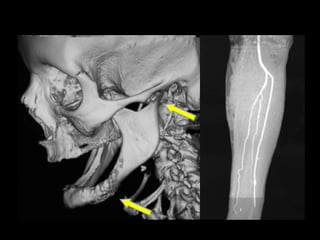

TC 3D

Hiperplasia condílea dcha

Anquilosis ATM dcha

Anquilosis ATM Hiperplasiacondílea Cirugía ortognática